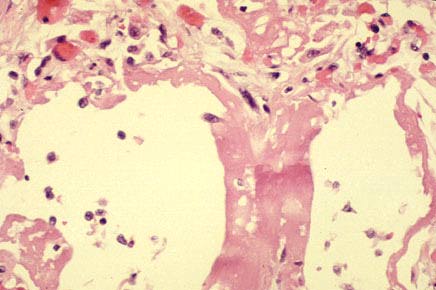

High power of fig. 25, acute ARDS.